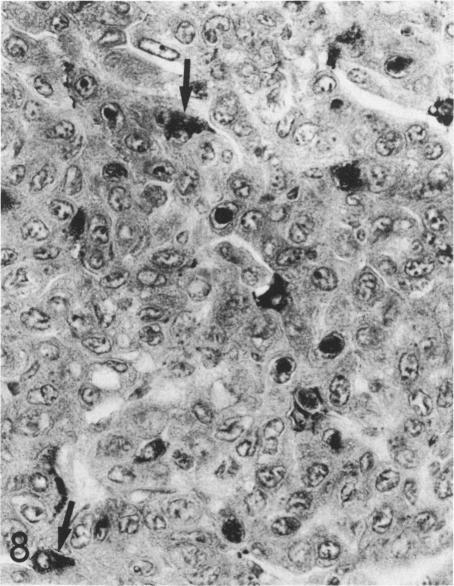

The localization of surfactant apoprotein (SAP) and the Clara cell antigen(s) (CCA) was studied in naturally occurring and experimentally induced pulmonary hyperplasias and neoplasms by avidin-biotin peroxidase complex (ABC) immunocytochemistry. Lungs of B6C3F1 and A strain mice with naturally occurring lesions, B6C3F1 mice given injections of N-nitrosodiethylamine (DEN), BALB/c nu/nu or nu/+ mice exposed transplacentally on Day 16 of gestation to ethylnitrosourea (ENU), or BALB/c nu/+ mice exposed to ENU at 8-12 weeks of age were preserved in formalin or Bouin's fixative. After ABC immunocytochemistry, SAP was found in the cytoplasm of normal alveolar Type II cells; in the majority of cells in focal alveolar and solid hyperplasias originating in peribronchiolar or peripheral locations; and in solid, tubular, papillary, and mixed adenomas and carcinomas. The larger mixed-pattern neoplasms and small or large tubular neoplasms usually had the least number of cells with SAP. The majority of large papillary adenomas and carcinomas in BALB/c mice exposed to ENU and in untreated A strain mice contained SAP in the nuclei of many neoplastic cells but only in the cytoplasm of a few neoplastic cells. CCA was found in normal Clara cells of bronchi and bronchioles but not in any hyperplastic or neoplastic lesion of any mouse studied. This study provided immunocytochemical evidence that the vast majority of naturally occurring and experimentally induced pulmonary neoplasms of mice are alveolar Type II cell adenomas and carcinomas.

采用抗生物素蛋白-生物素过氧化物酶复合物(ABC)免疫细胞化学方法,研究了表面活性物质载脂蛋白(SAP)和克拉拉细胞抗原(CCA)在自然发生和实验诱导的肺增生及肿瘤中的定位。对患有自然病变的B6C3F1和A品系小鼠、注射N-亚硝基二乙胺(DEN)的B6C3F1小鼠、在妊娠第16天经胎盘暴露于乙基亚硝基脲(ENU)的BALB/c裸鼠或裸+/+小鼠,或在8-12周龄时暴露于ENU的BALB/c裸+/+小鼠的肺组织,用福尔马林或布因氏固定液保存。经过ABC免疫细胞化学检测,发现SAP存在于正常肺泡II型细胞的细胞质中;存在于起源于细支气管周围或周边部位的局灶性肺泡增生和实性增生的大多数细胞中;也存在于实性、管状、乳头状和混合性腺瘤及癌中。较大的混合型肿瘤和小或大的管状肿瘤中通常含SAP的细胞数量最少。在暴露于ENU的BALB/c小鼠和未经处理的A品系小鼠中的大多数大乳头状腺瘤和癌,在许多肿瘤细胞的细胞核中含有SAP,但仅在少数肿瘤细胞的细胞质中含有。在支气管和细支气管的正常克拉拉细胞中发现了CCA,但在所研究的任何小鼠的增生性或肿瘤性病变中均未发现。本研究提供了免疫细胞化学证据,表明小鼠中绝大多数自然发生和实验诱导的肺肿瘤是肺泡II型细胞腺瘤和癌。